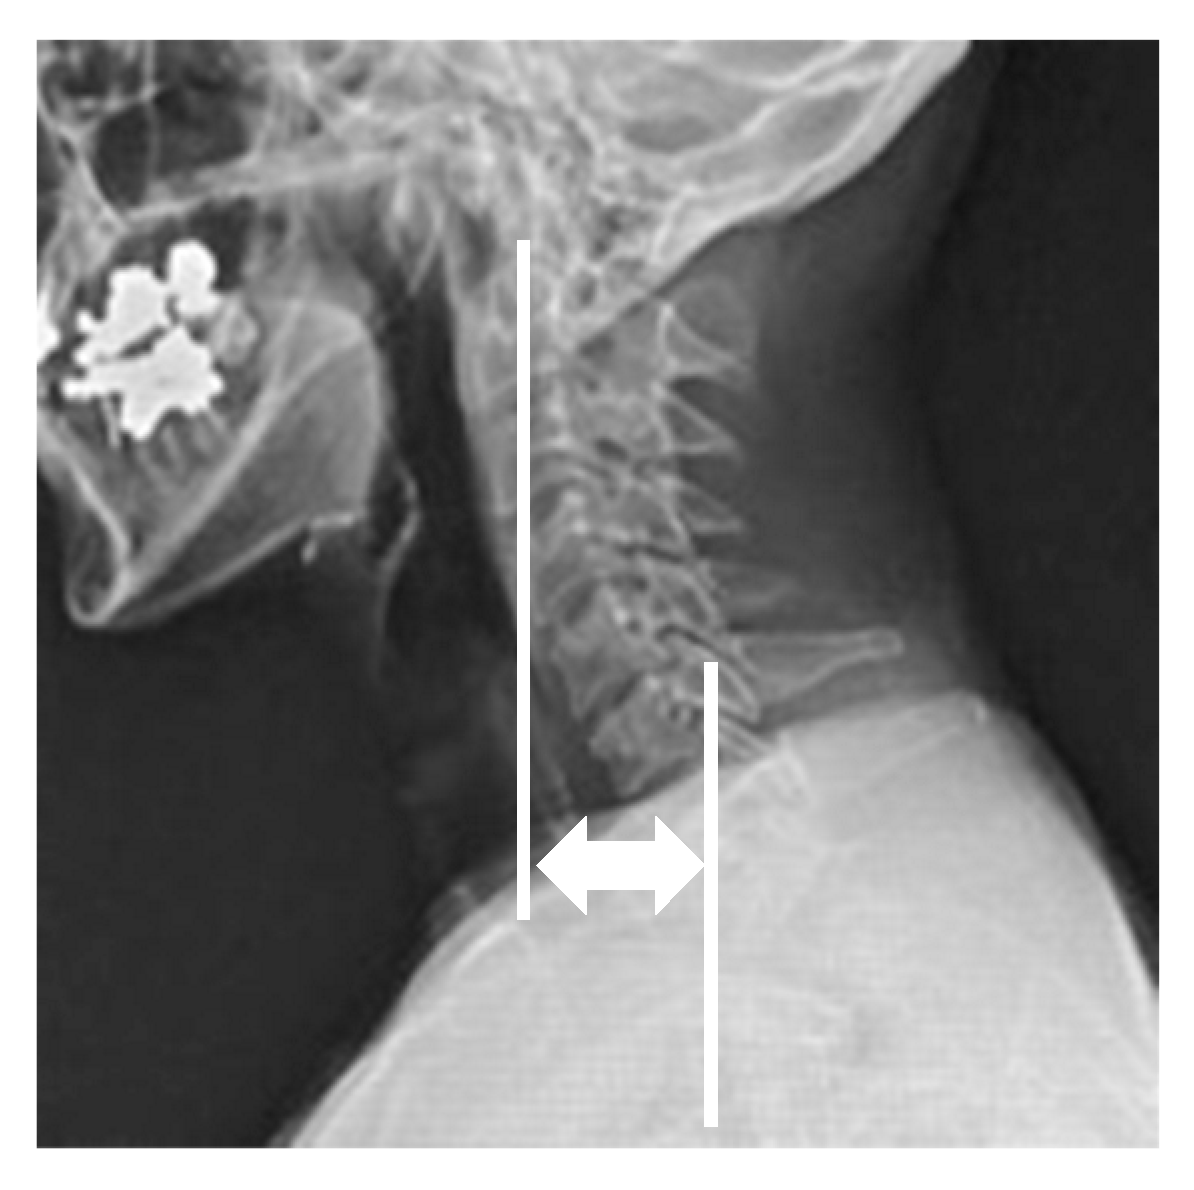

3.6. Representative Case of Unipolar Release of Sternocleidomastoid Muscle

Forty-year-old male. He had no past medical history except for his neglected CMT. He complained of head tilt and restriction of cervical range of motion, as well as neck pain and shoulder stiffness. He presented with a marked head tilt and thickened sternal and clavicular branches of the left SCM. The patient underwent a unipolar release of SCM. His radiographic parameters improved from baseline to final follow-up: CMA from 22° to 2°, C2 to T1 distance from 26 mm to 2 mm, clavicle angle from 2° to 0°, CSVL from 4 mm to 0 mm, cervical range of motion from 64° to 79°, and C2–7 SVA from 46 to 13 mm (Figure 4).

Figure 4.

Forty-year-old male was treated with unipolar release of the sternocleidomastoid. Pre- (a,b,e,g) and postoperative (c,d,f,h) appearance, radiographs, and intraoperative photographs. The head was markedly tilted to the left side, and the neck was shifted to the right side preoperatively. Left lower ends of the sternal branch and clavicular branch of the SCM were released at two incisions (i,j). There were good improvements in appearance and postoperative X-rays after the unipolar release of SCM.